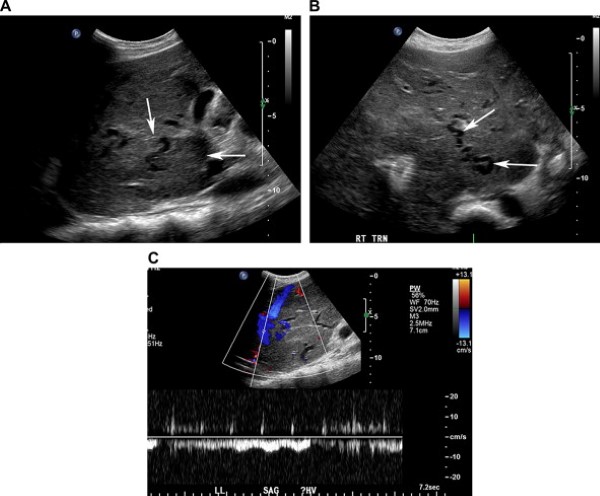

Nên nghĩ tới hội chứng Budd-Chiari khi siêu âm thang xám không nhìn thấy các tĩnh mạch gan. Các dấu hiệu thêm vào gồm có thành tĩnh mạch gan dày, khẩu kính các tĩnh mạch không đều, và tĩnh mạch bàng hệ ngoằn ngoèo. Bệnh nhân hhường kèm theo gan to và tràn dịch ổ bụng. Phì đại chủ yếu ở thùy đuôi là đặc trưng và thường xảy ra do dẫn lưu tĩnh mạch của nó biệt lập đổ vào tĩnh mạch chủ dưới (bên dưới hội lưu tĩnh mạch gan).

Siêu âm Doppler phổ và màu chứng minh không có dòng chảy, dòng chảy giảm tốc độ, đảo ngược dòng chảy hoặc dòng chảy rối với tốc độ tăng cao trong các tĩnh mạch gan [23]. Khi có dòng chảy trong các tĩnh mạch gan và tĩnh chủ dưới, thì hình dạng sóng từ ba pha chuyển thành dạng phẳng giống như tĩnh mạch cửa –“tín hiệu Doppler giả tĩnh mạch cửa”, phản ánh bán tắc xuôi dòng [1,25]. Tuy nhiên kiểu sóng này không đặc hiệu, và có thể gặp trong các tình trạng bệnh lý gây tăng áp lực trong nhu gan, như thâm nhiễm mỡ, viêm gan cấp, và xơ gan [25].

Khoảng 50% các bệnh nhân Budd-Chiari phát hiện tĩnh mạch thùy đuôi to với đường kính trên 3 mm, và dấu hiệu này được coi là đặc trưng khi không có suy tim (Hình 21) [25]. Tĩnh mạch này giãn là do thùy đuôi là thùy duy nhất trong gan dẫn lưu trực tiếp vào tĩnh mạch chủ dưới, và nó còn làm cầu nối tắt nhận máu của các nhánh bàng hệ trong nhu mô gan còn lại nên dẫn tới phì đại thùy đuôi và tĩnh mạch thùy đuôi [25].

Hình 21. Hội chứng Budd-Chiari ở bệnh nhân nam 30 tuổi có tiền sử hemoglobin niệu kịch phát về đêm và xuất hiện sưng phồng ổ bụng. (Hình A) Siêu âm màu phát hiện hẹp tĩnh mạch gan giữa với aliasing mầu gân chỗ nối của nó với tĩnh mạch chủ dưới (mũi tên). (Hình B) Ảnh siêu âm màu và Doppler cho thấy tĩnh mạch gan giữa thông, nhưng tốc độ dòng chảy tăng cao. (Hình C) Ảnh siêu âm màu cho thấy tĩnh mạch thùy đuôi to (mũi tên) tĩnh mạch của nó dẫn lưu trực tiếp vào tĩnh mạch chủ dưới. Hình ảnh cộng hưởng từ và sinh thiết gan xác định hội chứng Budd-Chiari.

Chứng minh các nhánh bàng hệ tĩnh mạch-tĩnh mạch trong gan là dấu hiệu đặc trưng của hội chứng Budd-Chiari và có thể bao gồm các tĩnh mạch dưới bao gan, các mạch máu nối tắt giữa các tĩnh mạch gan, các nhánh bàng hệ tĩnh mạch-tĩnh mạch dẫn lưu trực tiếp vào tĩnh mạch chủ dưới, và các nhánh bàng hệ hình mạng nhện cổ điển (Hình 22) [23,25]. Sự phát triển của các nhánh bàng hệ cửa-chủ tự phát cũng có thể xảy ra và trong một số trường hợp có thể tránh phải làm thủ thuật nối tắt cửa-chủ trong gan theo đường tĩnh mạch cảnh (TIPS) [25].

Hình 22. Hội chứng Budd-Chiari ở bệnh nhân nữ 36 tuổi có tiền sử tăng hồng cầu vô căn và biểu hiện sưng, đau bụng. Trước đó bệnh nhân đã được đặt TIPS nhưng đã tắc. (Hình A) Ảnh thang xám cho thấy phì đại thùy đuôi (mũi tên) với nhiều cấu trúc ống, trống âm, ngoằn ngoèo trong gan. (Hình B) Nhiều cấu trúc ống trống âm trong gan. (Hình C) Ảnh Doppler màu xác định dòng chảy tĩnh mạch trong các tĩnh mạch bàng hệ đó.